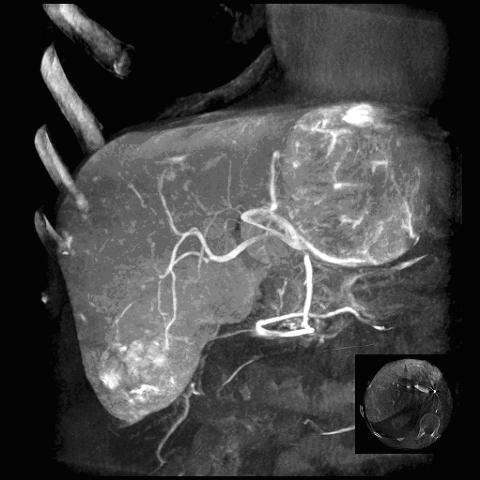

Артеріографія печінкової артерії

- проводиться для діагностики пухлин печінки та цирозу.